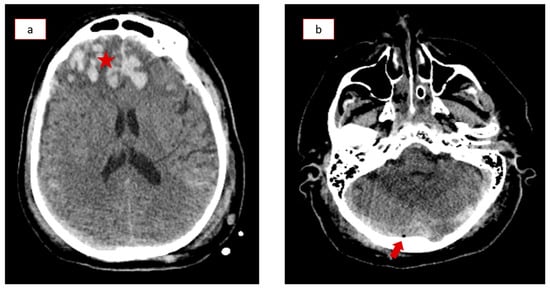

During his stay in the ICU, the patient also developed a cerebrospinal fluid (CSF) infection, which was successfully treated with broad-spectrum antibiotics. Despite his worsening clinical condition, the following series of brain CT scans showed continuous improvement of the initial traumatic hemorrhagic findings. The mismatch between his clinical and imaging findings raised suspicion for post-traumatic cerebral venous thrombosis, so the patient underwent a CT venography (CTV) on the 14th day of hospitalization. The CTV revealed left transverse sinus and sigmoid sinus thrombosis (Figure 2a,b), which were treated with anticoagulation therapy (high-dose enoxaparin) according to appropriate protocols (Supplementary Figure S1). The patient underwent a tracheostomy due to prolonged mechanical ventilation, and he was then transferred to the Neurosurgical Department, where a gradual neurological improvement was recorded (GCS of 14/15). He was discharged after thirty-eight days of hospitalization with only minor neurological deficits. The patient presented again with cerebrospinal fluid (CSF) rhinorrhea 36 days after discharge, while new CT scans indicated a bone lesion in the roof of the right ethmoid sinus, necessitating lumbar drain catheter insertion with a continuous flow target of 7–10 mL CSF per hour. He was finally discharged after nine days, and no other complications occurred during his following regular follow-ups.

Figure 2.

Computed tomography venography (CTV) on the 14th day in the Intensive Care Unit (ICU) revealing thromboses in the (a) left transverse and (b) sigmoid sinus (red arrows).